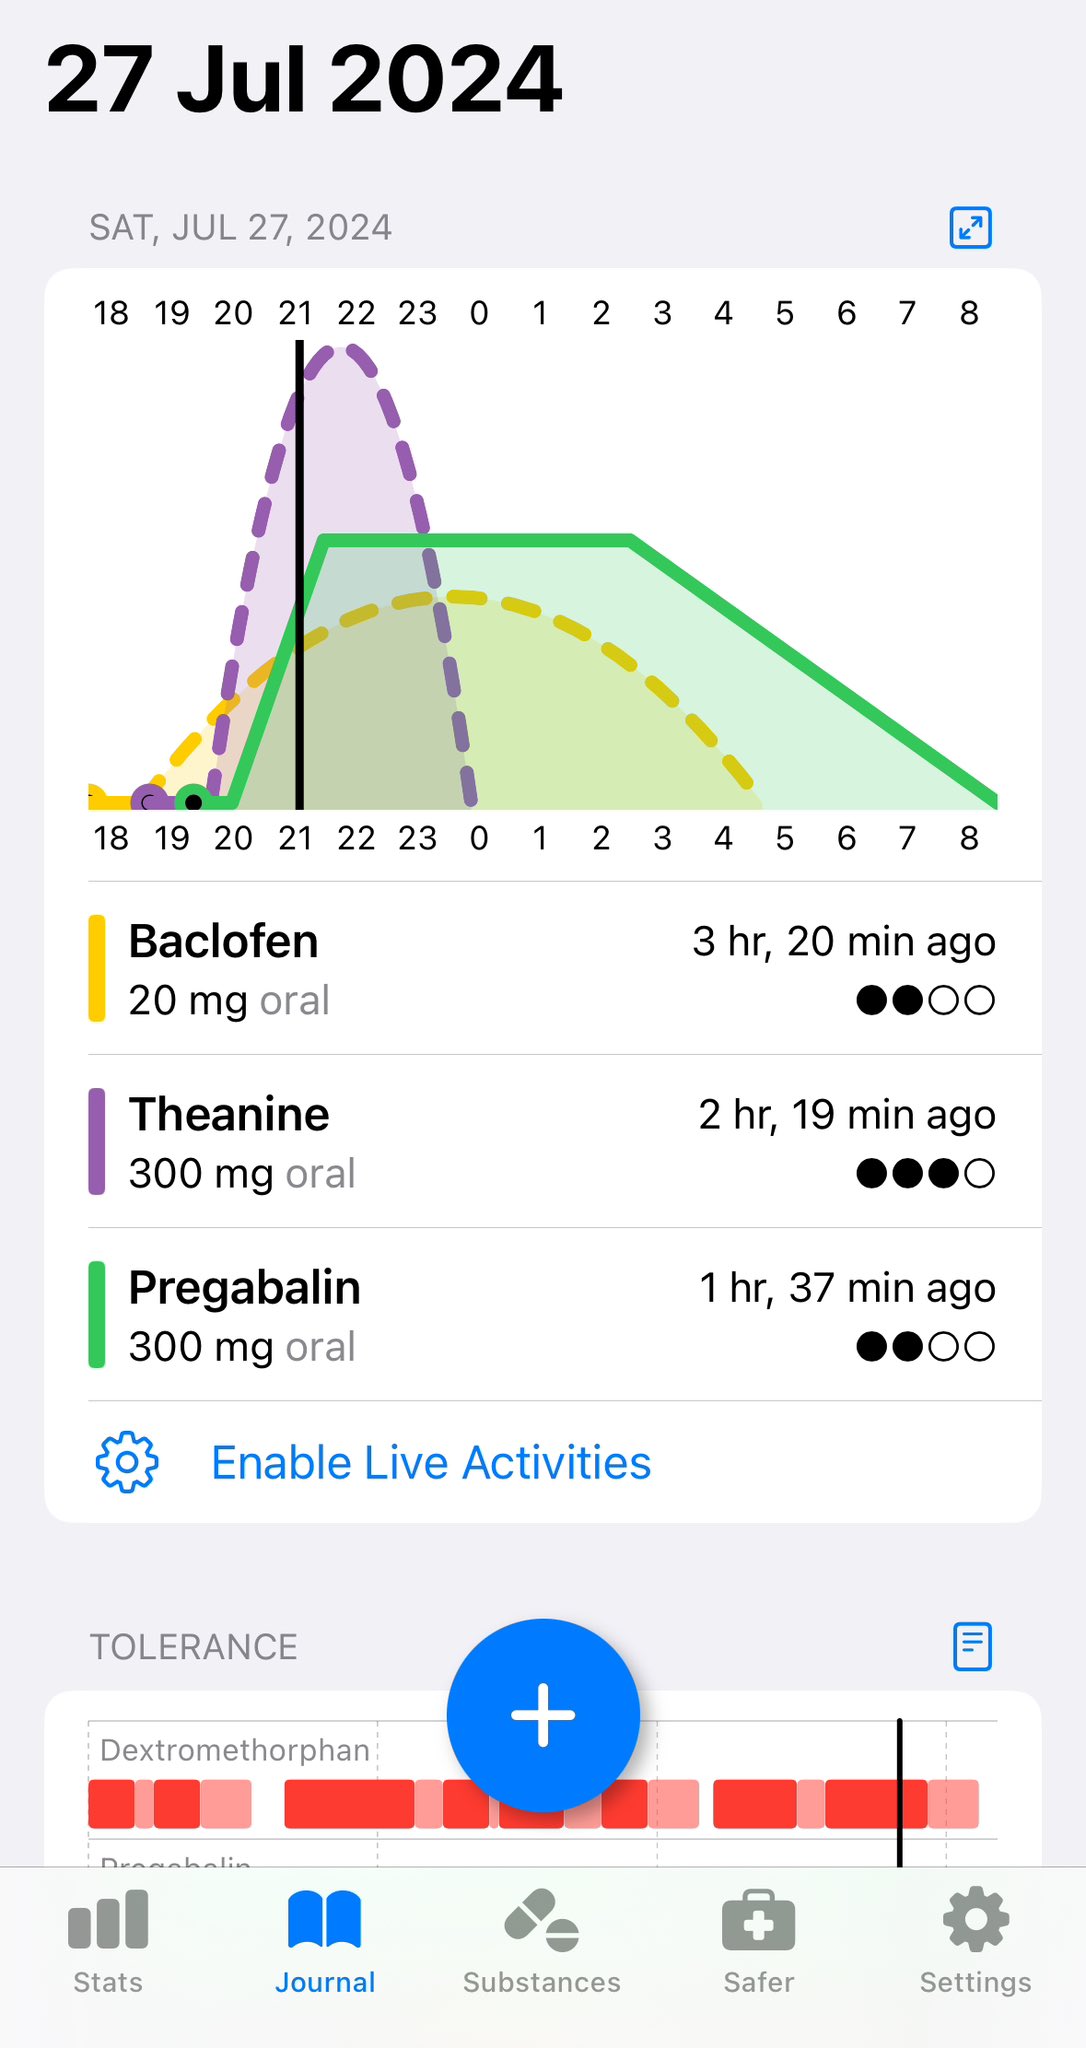

2024-08-14 11:34:53 UTC

甚至在第二天有余晖的感觉,虽然发生了很多破事但没怎么影响心情*抗焦虑&镇静

运动协调性稍差,表现为走路和站立时平衡不好

此剂量下对睡眠的改善作用,增加了慢波睡眠且没有影响rem,精力恢复+

FDA数据,在临床剂量下(75-600mg)普瑞巴林的依赖性低于bzd,并相比之下它产生的认知和精神运动障碍较轻 https://t.co/TJ7ZOQ7pbC